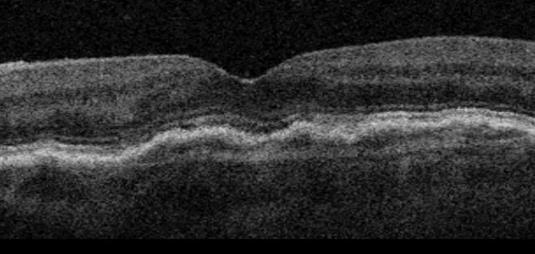

Kuivassa silmänpohjarappeumassa silmänpohjassa sijaitseva RPE-aistisolukerros, jossa näkemisen kannalta tärkeät tappi- ja sauvasolut sijaitsevat, alkaa rappeutumaan ja menee monesti poimuiseksi, joka hankaloittaa tarkkaa näkemistä. Pitkälle edenneessä kuivassa silmänpohjarappeumassa puolestaan RPE-kerros atrofisoituu, eli surkastuu, keskeiseltä näkökentältä lähes kokonaan, jolloin ihminen ei kykene enää ilman suurentavia apuvälineitä tarkkaan näkemiseen. Yleensä tällainenkaan tilanne ei täysin kokonaan sokeuta, sillä surkastuminen vain hyvin harvoissa tapauksissa yltää ääreisnäkemisen alueelle. Kuivaan silmänpohjarappeumaan ei nykylääketiede tunne tarkkaa syytä ja sitä ei osata parantaa. Terveet elämäntavat, terveellinen ruokavalio ja tietyt mm. luteenipitoiset lisäravinteet auttavat kuitenkin hillitsemään sen etenemistä. Nykyisin tutkitaan myös tiettyjen valohoitomuotojen vaikutusta kuivaan silmänpohjarappeumaan.

Kuiva silmänpohjan ikärappeuma

Atrofisoitunut kuiva silmänpohjarappeuma